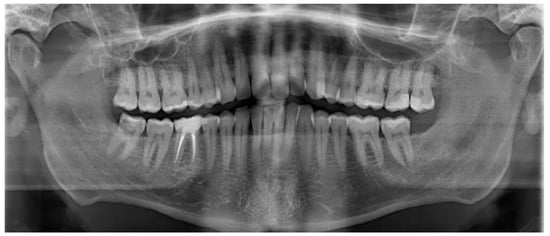

| 1 | Male | 48 | Osteoma of the coronoid process |

OPG CT | 19 mm | Coronoidectomy | 39 mm |

| 2 | Female | 10 | Bilateral hyperplasia of the coronoid processes |

OPG CT | 17 mm | Bilateral coronoidectomy | 45 mm |